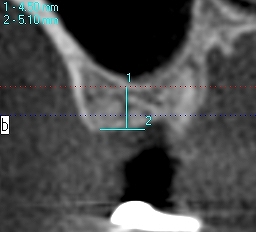

上顎洞までの距離はしっつかりとあるわけでもありません

この骨に上顎洞を持ち上げ5㎜幅10㎜長さのインプラントを埋入

していきました